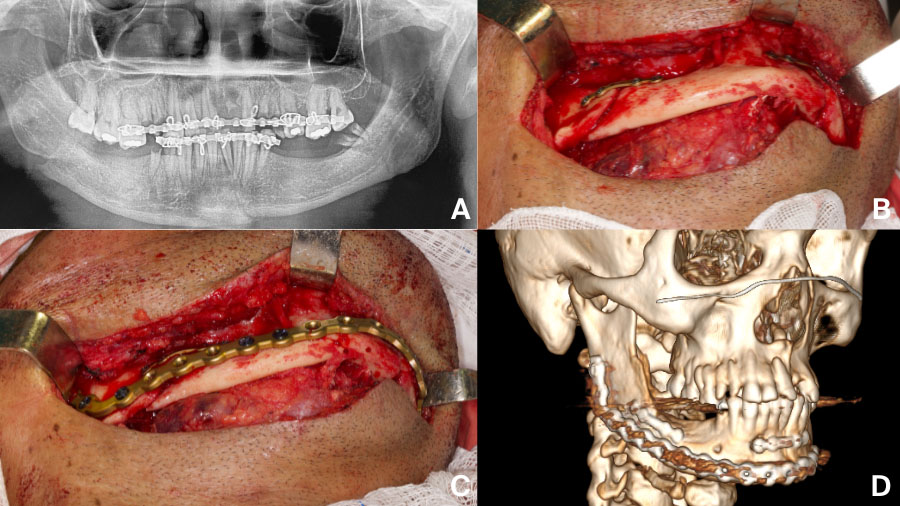

Case examples and lessons learned

Real-world cases reveal the diverse and often complex challenges in managing mandibular fractures complications. Each highlights the technical precision and clinical judgment required for successful outcomes and reminds us that even expertly executed care can face complications, especially in severe trauma or difficult anatomy.

Clinical examples and the spectrum of complications:

- Gunshot injuries often demand immediate airway control and staged reconstruction.

- Comminuted or atrophic fractures require load-bearing plates and generous exposure.

- Malunion after inadequate fixation may be salvaged with revision surgery

- Nonunion

- Persistent infection is often a sign of instability or hardware failure

Reflecting on these cases, it becomes clear that complications are not always a reflection of suboptimal care, but frequently stem from the complexity of the injury and the limitations of current techniques. The most important lessons are the value of early recognition, proactive intervention, and continuous learning, each of which plays a critical role in achieving the best possible outcomes for patients.